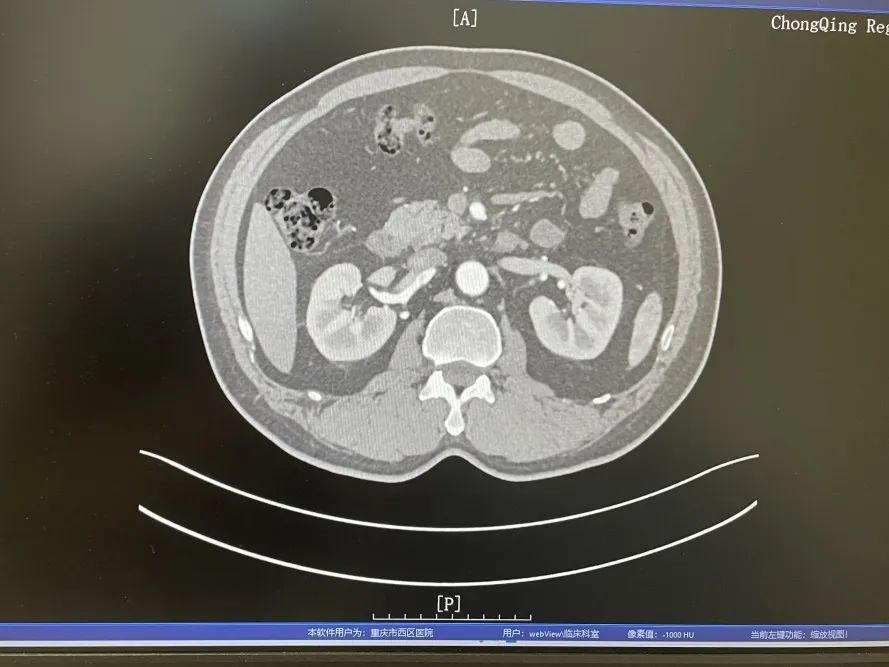

明确病因以后,心血管外科主任李炜迅速召集手术团队,经过综合讨论及与患者家属的充分沟通后,决定先为患者保守治疗,再根据患者检查结果考虑是否为患者行手术治疗。在为期三天的保守治疗后,腹痛已经缓解,复查下腹部CTA,检查结果显示患者情况无变化,于是决定为患者行右肾动脉造影+肠系膜上动脉造影+支架植入术。

治疗前

治疗后